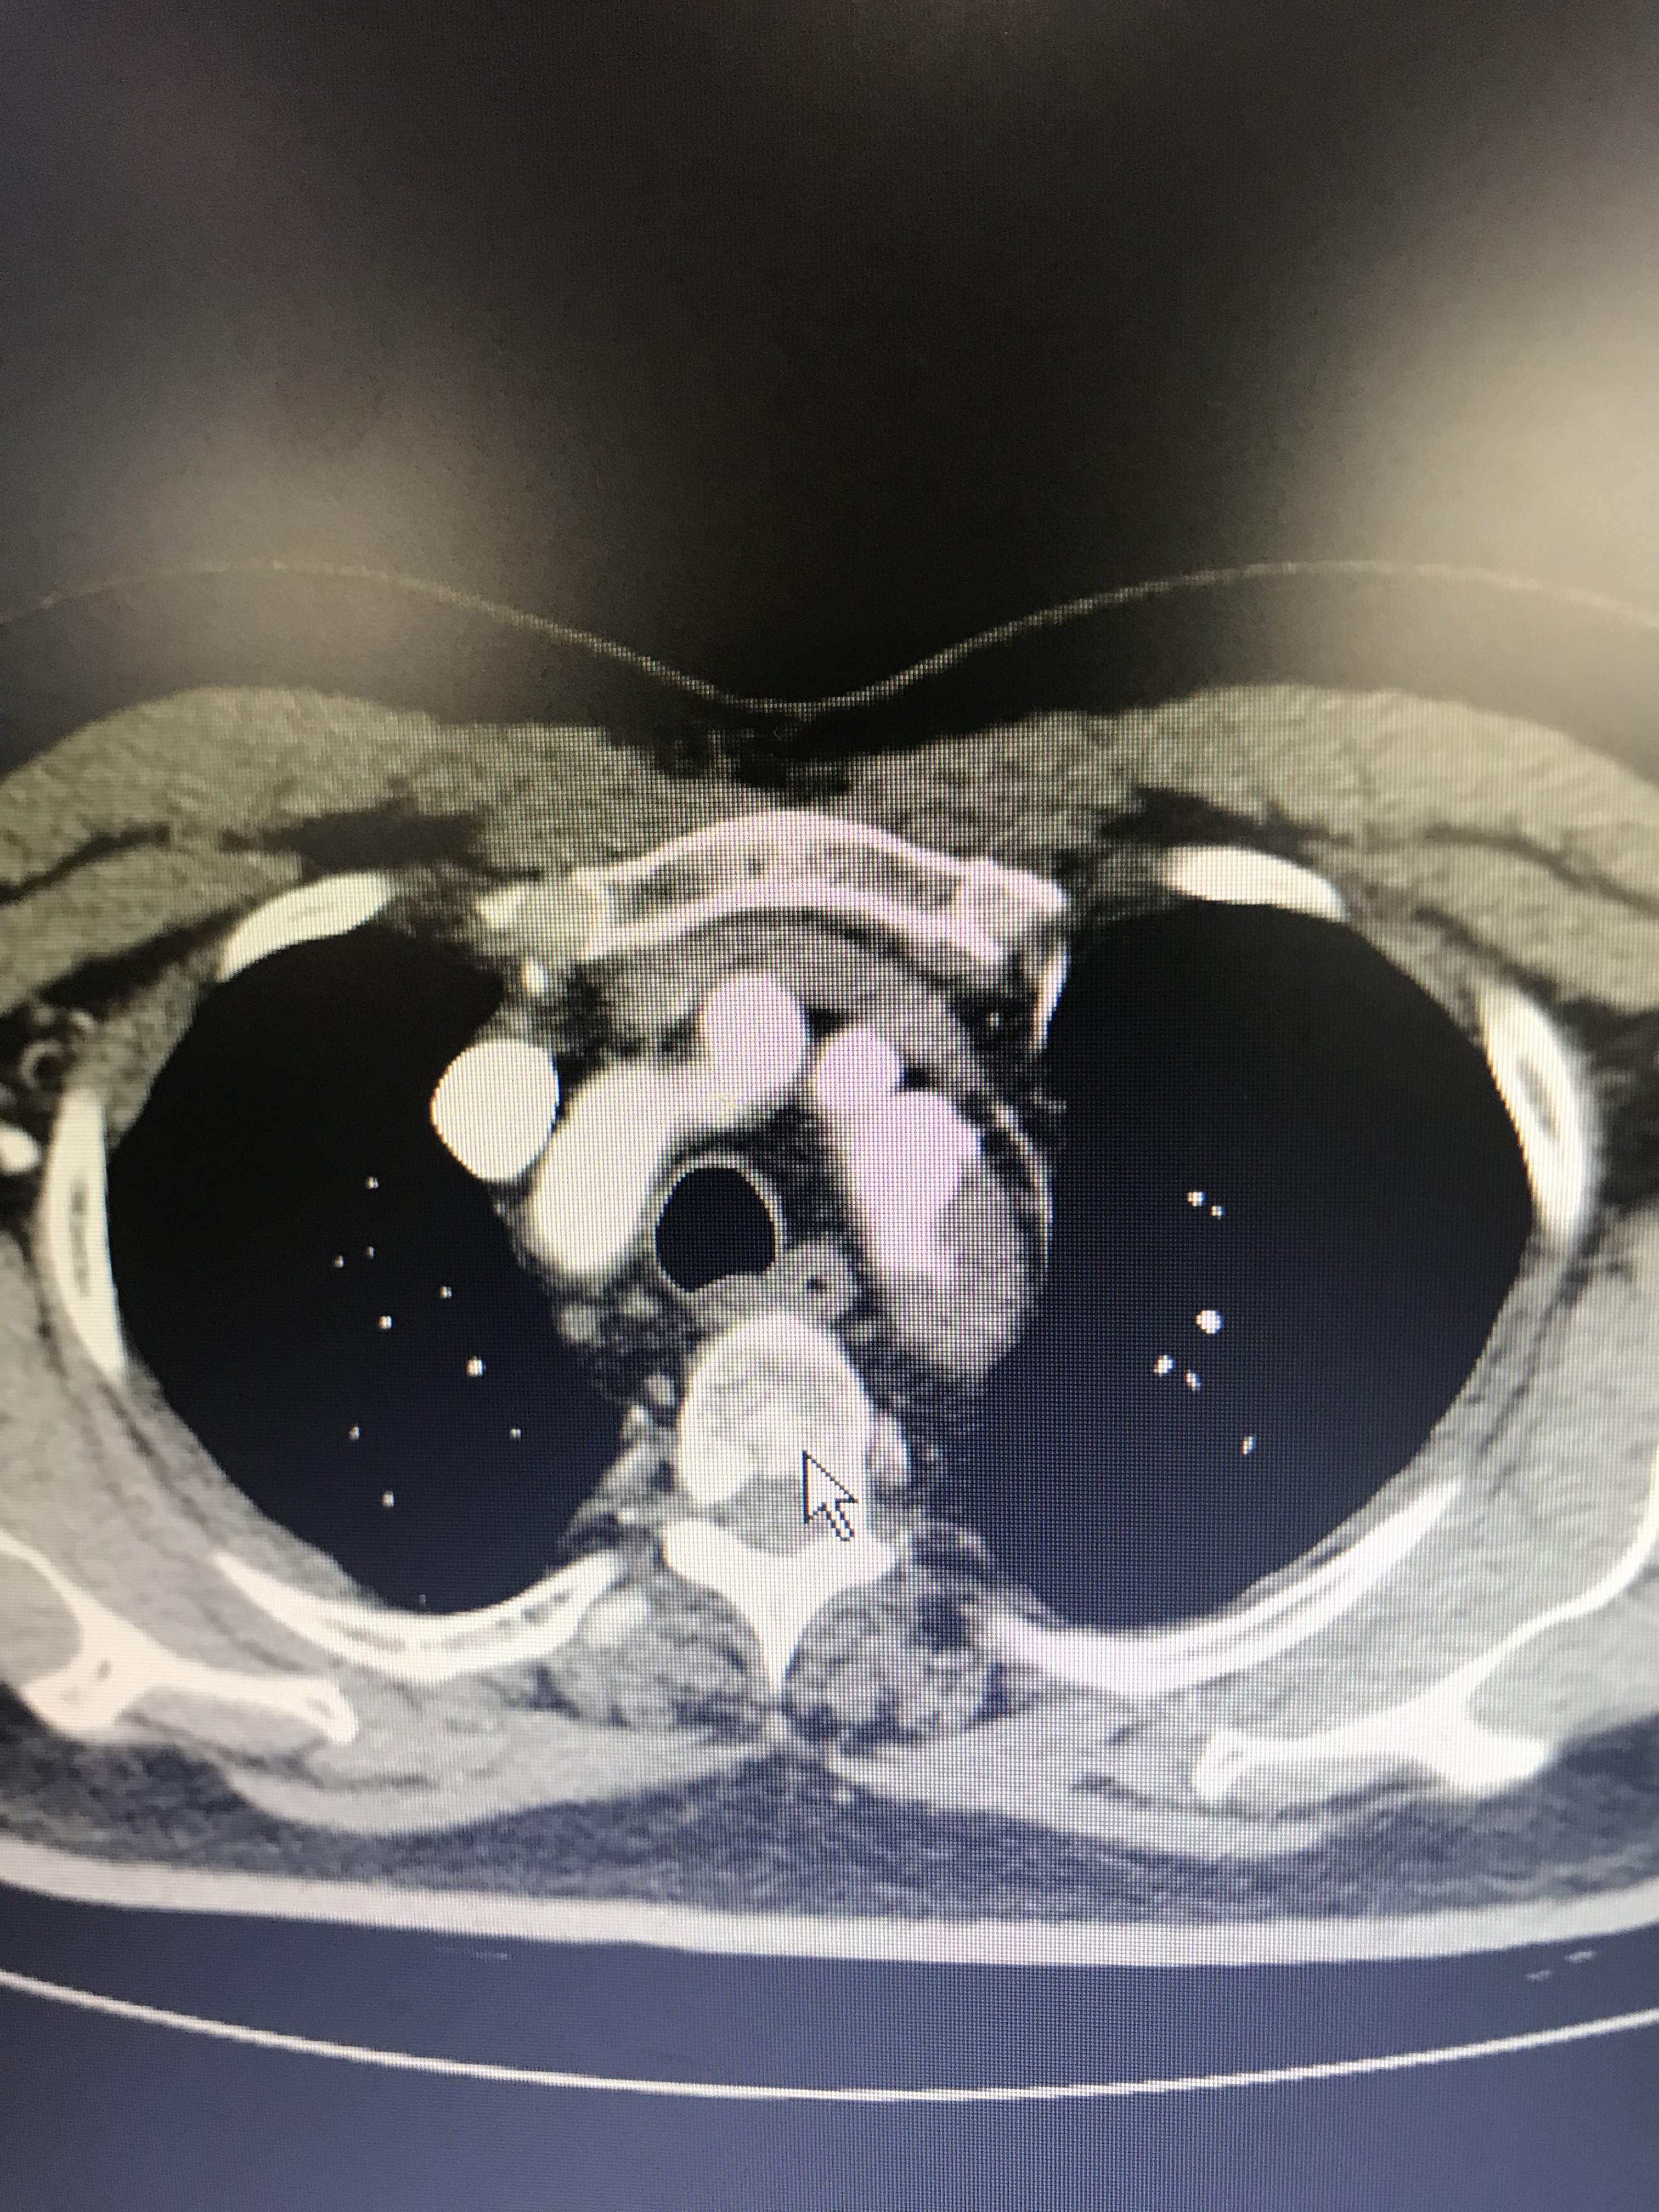

病人胸痛,这图像竟然不是主动脉溃疡?

大家帮我忙看看,到底是不是主动脉溃疡?